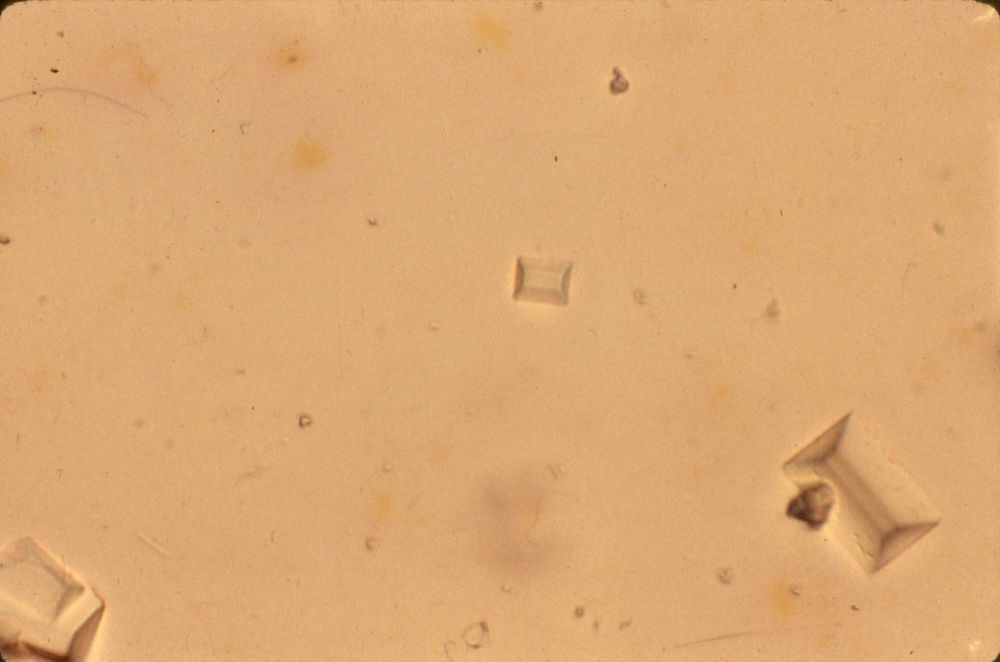

Image:

Ca Oxalate Hp (image/jpeg)

Calcium Oxalate hp |